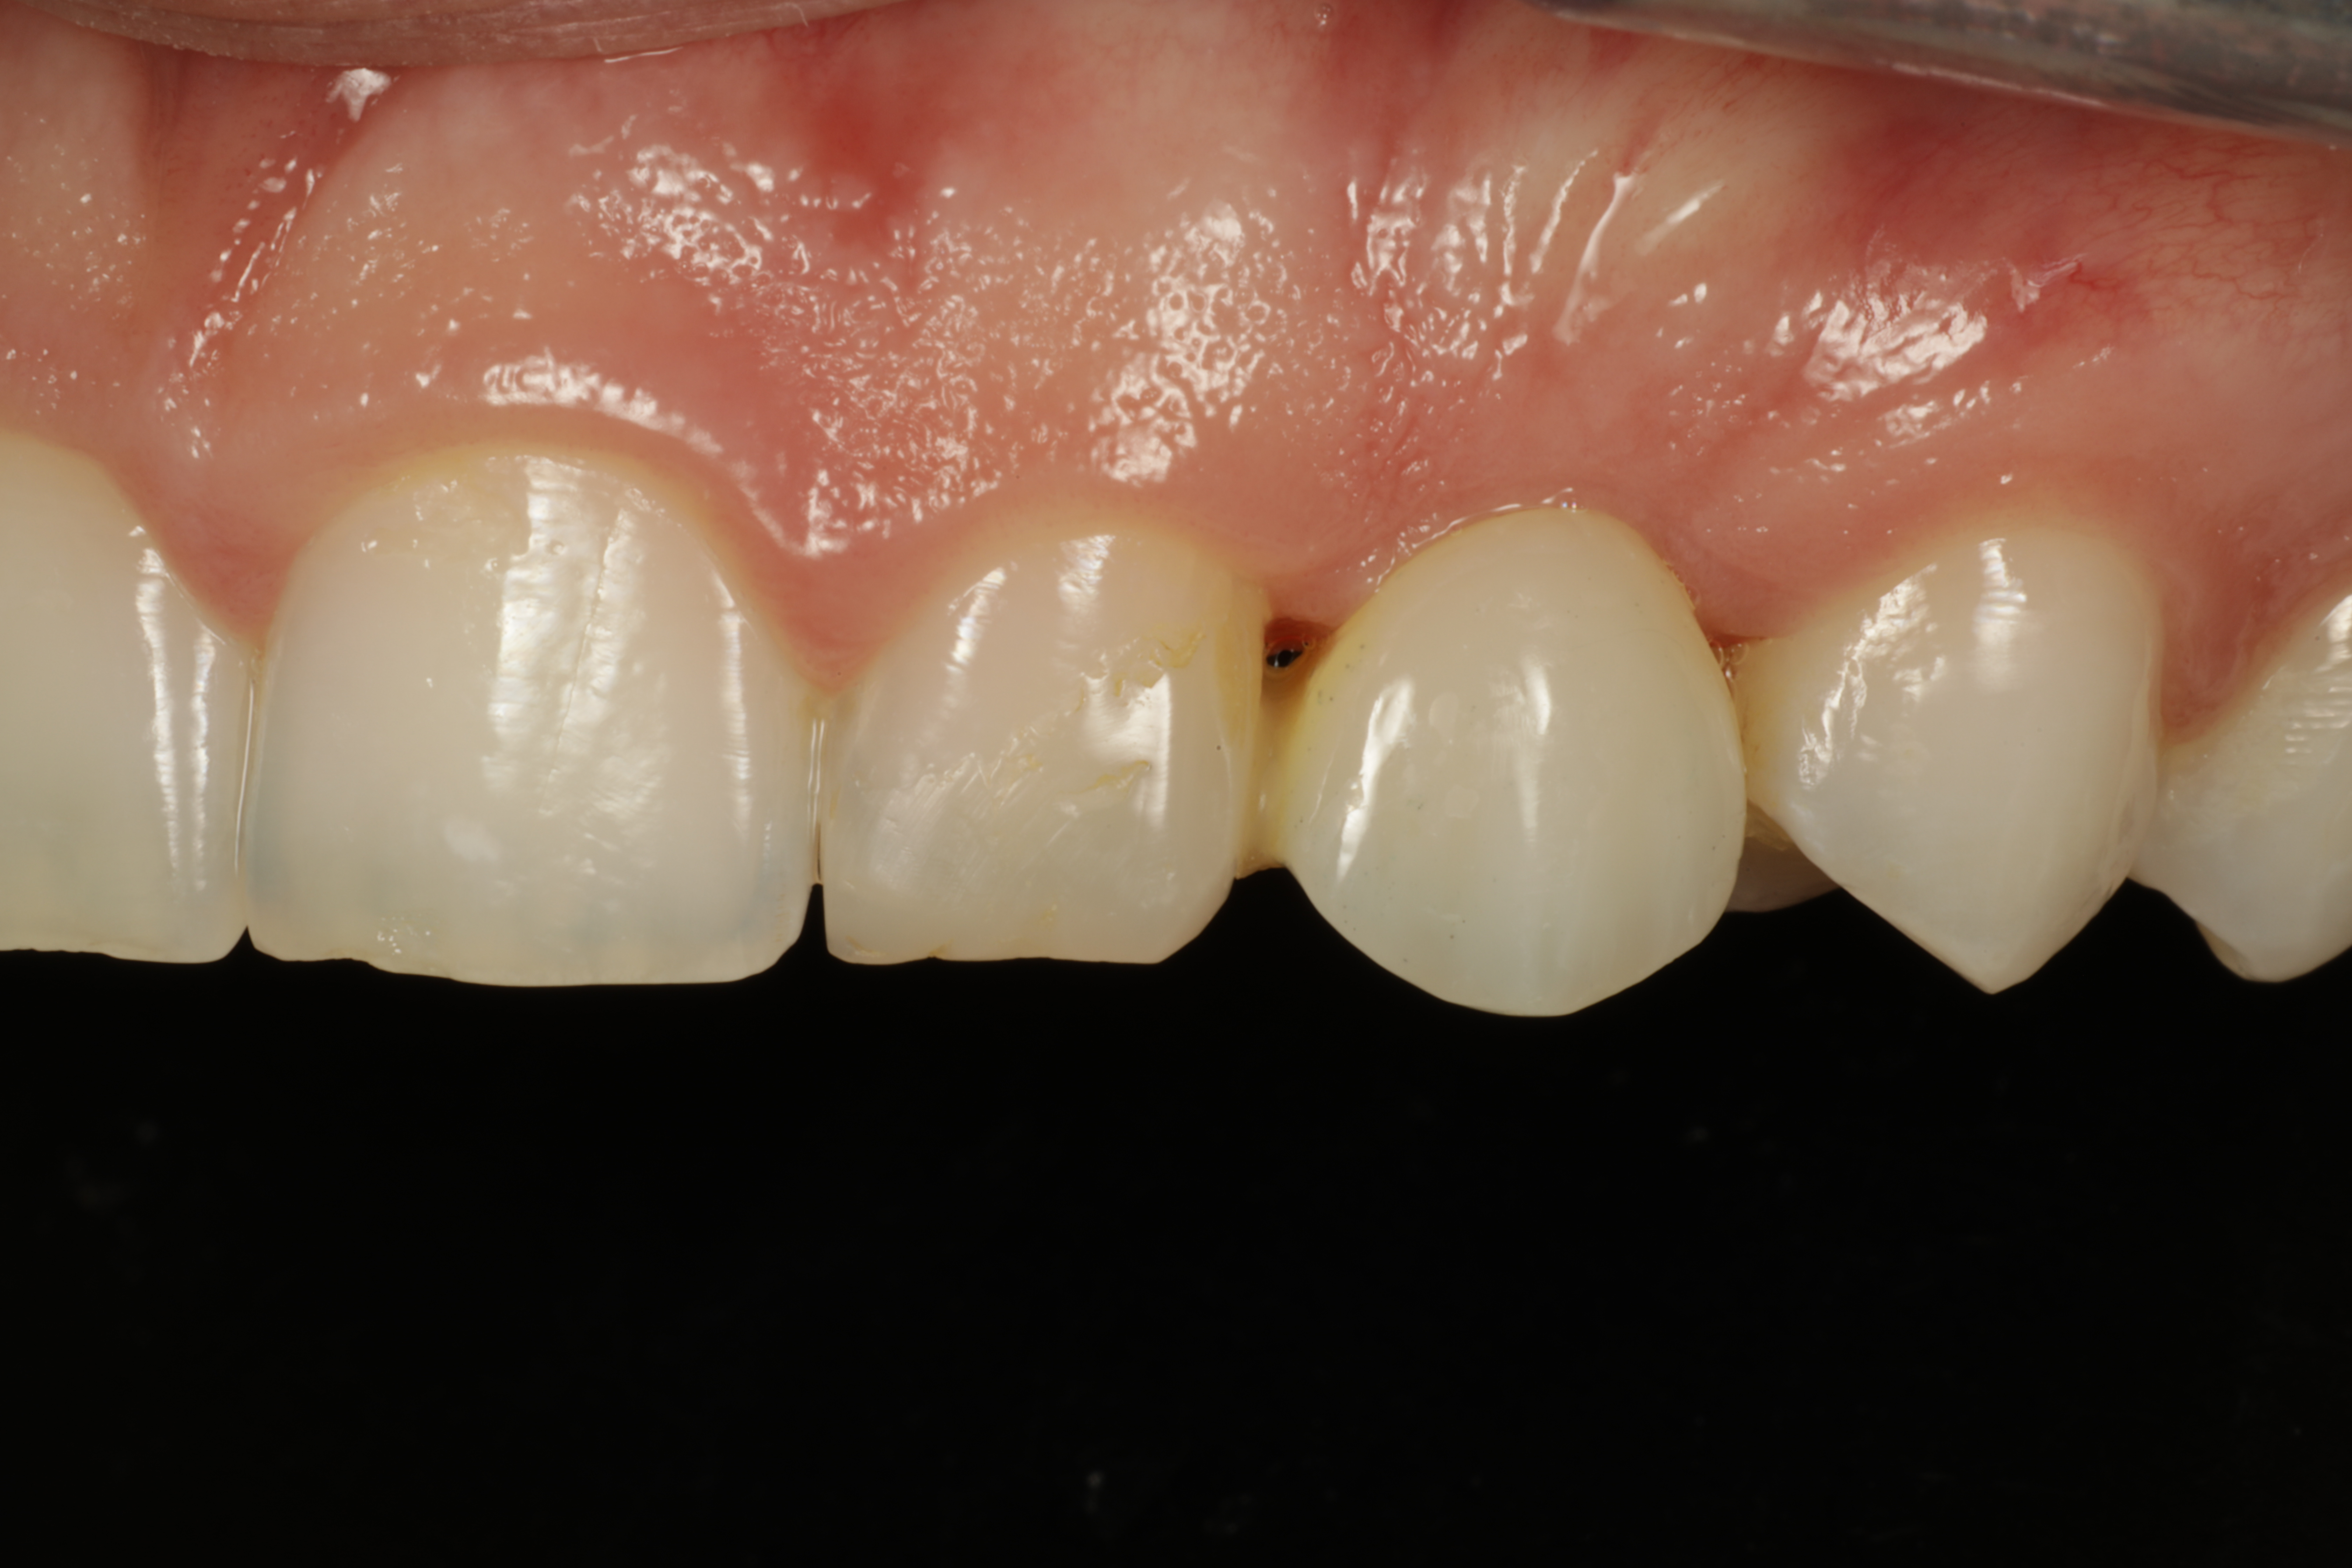

Alkutilanne läheltä

Synnynnäisesti puuttuva kulmahammas. Alkukuvissa hammas on korvattu muovisella kevytsillalla. Silta purettu pois ja asetettu implantti puuttuvan hampaan tilalle. Kirurgina Jarno Savolainen eSmile Helsinki. Hammasteknikkomestari Aki Lindén.